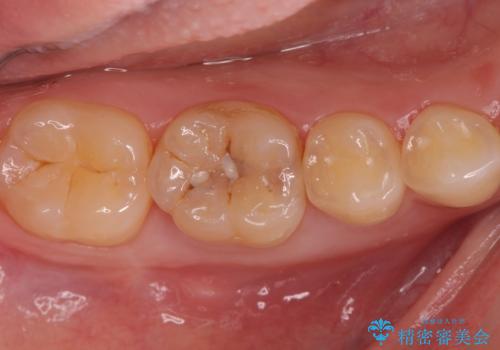

奥歯が欠けた セラミックインレーでの修復後、ナイトガード装着

![[e-maxインレー] 矯正治療前の虫歯治療の症例 治療後](https://seimitsushinbi.jp/wp/wp-content/uploads/2023/08/IMG_2869-1-500x350.jpg?v=1691812292)